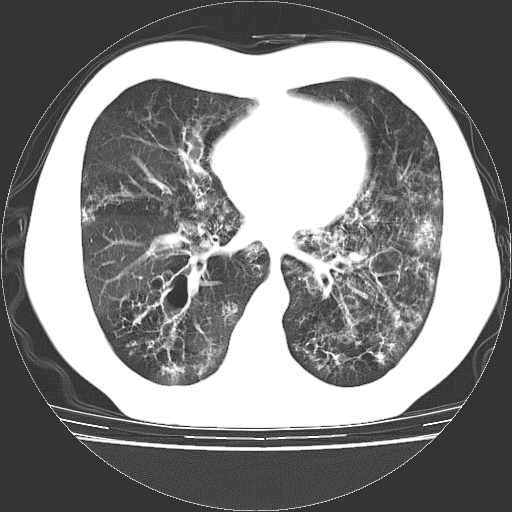

以下是引用zyx168在2006-12-4 15:30:00的发言:[br]经典!支气管肺囊肿并感染。

以下是引用dyqct在2006-12-4 17:11:00的发言:[br]典型的囊状支扩合并感染。

以下是引用liaoqiang在2006-12-4 16:12:00的发言:[br]局部肺叶内可见扩张的支气管壁,考虑为支扩。部份囊样影内有小液平和肺内散布斑片征影、小结节及纤维灶,提示支扩伴感染,且由于局部呈现有树芽征感染以结核可能性大。

以下是引用zhoucan076在2006-12-4 16:48:00的发言:[br]囊状支扩合并感染